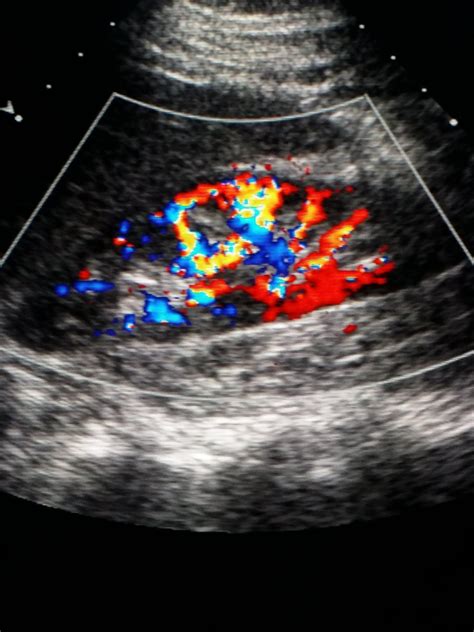

Kidney Ultrasound Process at Sophie Clarkson blog